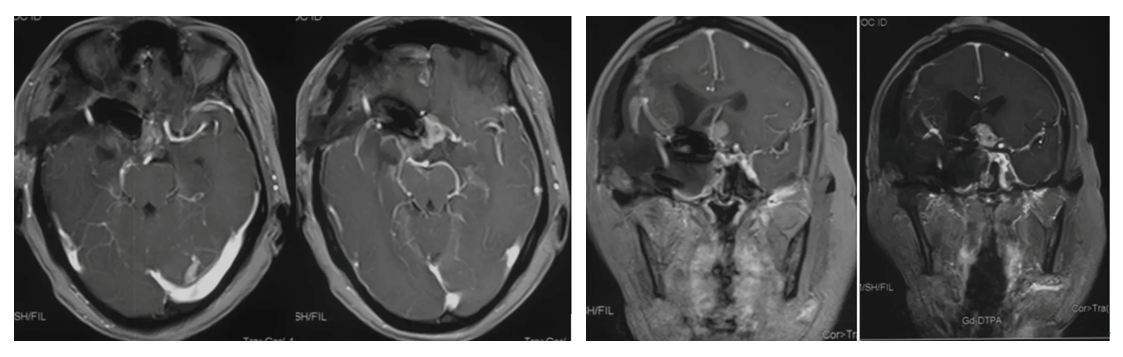

Cranial MRI enhanced

1. MRI T1 and T2 images showed a tumor in the left saddle region with long T1 and short T2 signals. The tumor was solid and encircled the internal carotid artery and branch vessels.

2. Enhanced axial and coronal-sagittal views showed that the tumor was unevenly enhanced, which was located in the saddle region, invaded the right cavernous sinus, and encircled the internal carotid artery and its branches and perforating vessels.